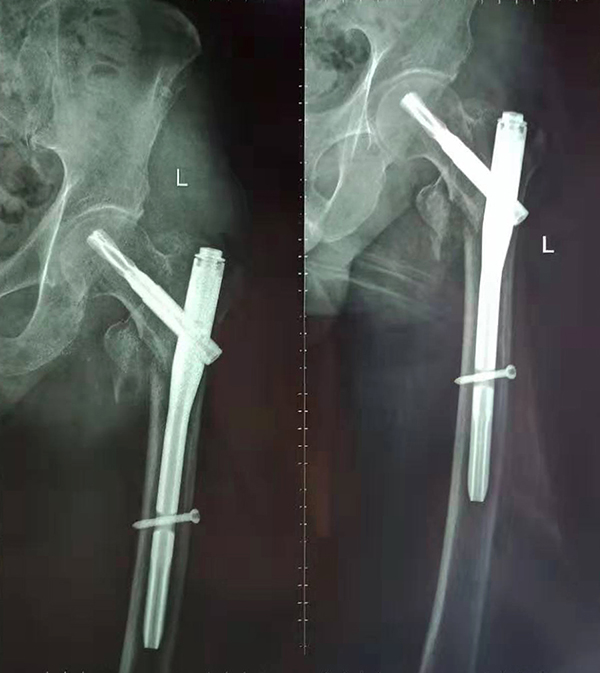

經(jīng)術(shù)前仔細(xì)的檢查和評估,與張爺爺家屬充分溝通,決定了實(shí)施閉合復(fù)位PFNA內(nèi)固定術(shù)的方案,劉鴻程主任說到,該術(shù)式的創(chuàng)傷小、出血少,適合骨質(zhì)疏松病人,術(shù)后解除患者疼痛,可以早期開始活動,便于護(hù)理。

手術(shù)前

手術(shù)后

9月10日上午,骨科順利完成張爺爺?shù)淖蠊晒谴致¢g骨折髓內(nèi)釘內(nèi)固定術(shù)。手術(shù)過程中麻醉平穩(wěn),術(shù)中出血量少,骨折手術(shù)時(shí)間持續(xù)一個多小時(shí)。